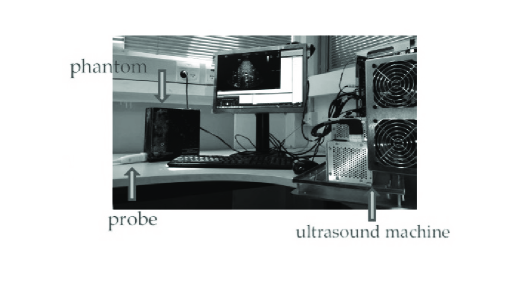

VI-B Implementation on Stand Alone Imaging System

As a next step we implemented low-rate frequency domain beamforming on an ultrasound imaging system [29]. The lab setup used for implementation and testing is shown in Fig. 8 and includes a state of the art GE ultrasound machine, a phantom and an ultrasound scanning probe. In our study we used a breadboard ultrasonic scanner with 64 acquisition channels. The radiated depth cm and speed of sound m/sec yield a signal of duration sec. The acquired signal is characterized by a narrow bandpass bandwidth of MHz, centered at a carrier frequency MHz. The signals are sampled at the rate of MHz and then are digitally demodulated and down-sampled to the demodulated processing rate of MHz, resulting in real-valued samples per transducer element. Linear interpolation is then applied in order to improve beamforming resolution, leading to real valued samples. Fig. 9 presents a schematic block diagram of the transmit and receive front-end of the medical ultrasound system being used.